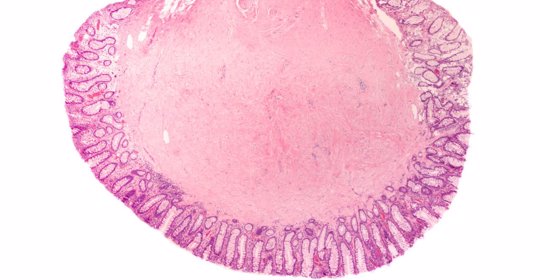

本文介紹了腸炎的非藥物治療方法。患者可遵醫囑使用補液鹽溶液、口服舒腹達(Diosmectite)、抗生素治療、益生菌補充劑、靜脈吊點滴等方法來改善病情。若症狀沒有得到緩解或者加重,則應及時就醫接受專業治療。對於腸炎的藥物治療,通常需要在醫師指導下進行,常用藥物有舒腹達(Diosmectite)、雙歧桿菌製劑、枯草桿菌製劑、諾弗灑欣(Norfloxacin)、阿莫西林(Amoxicillin)等。